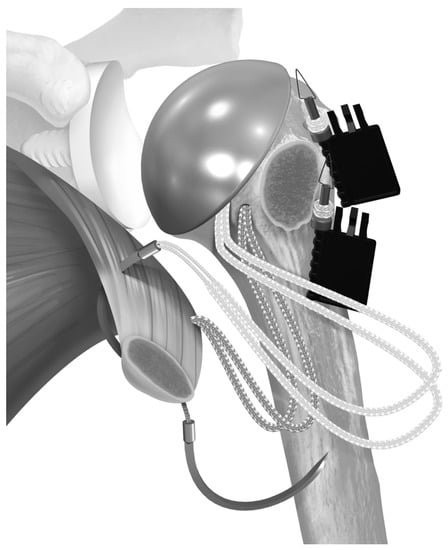

2.2. Surgical Technique